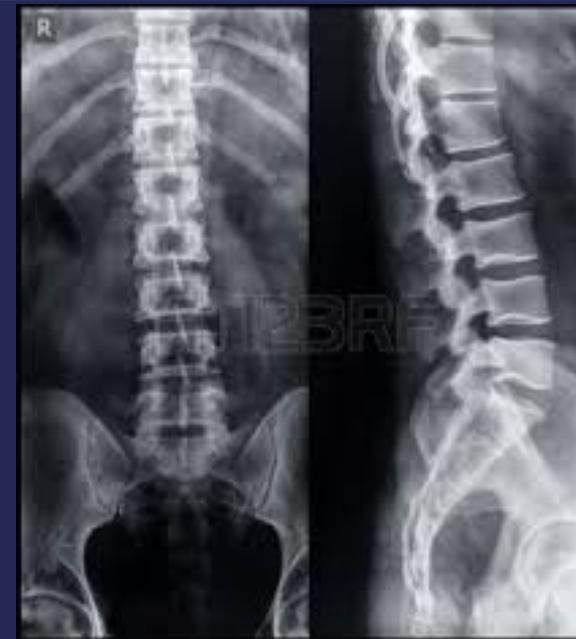

Imaging for Spinal Disorders

X-Ray

- AP, LAT, OBLIQUE views

- Flexion-Extension LAT

- Deformity series (e.g., scoliosis series)